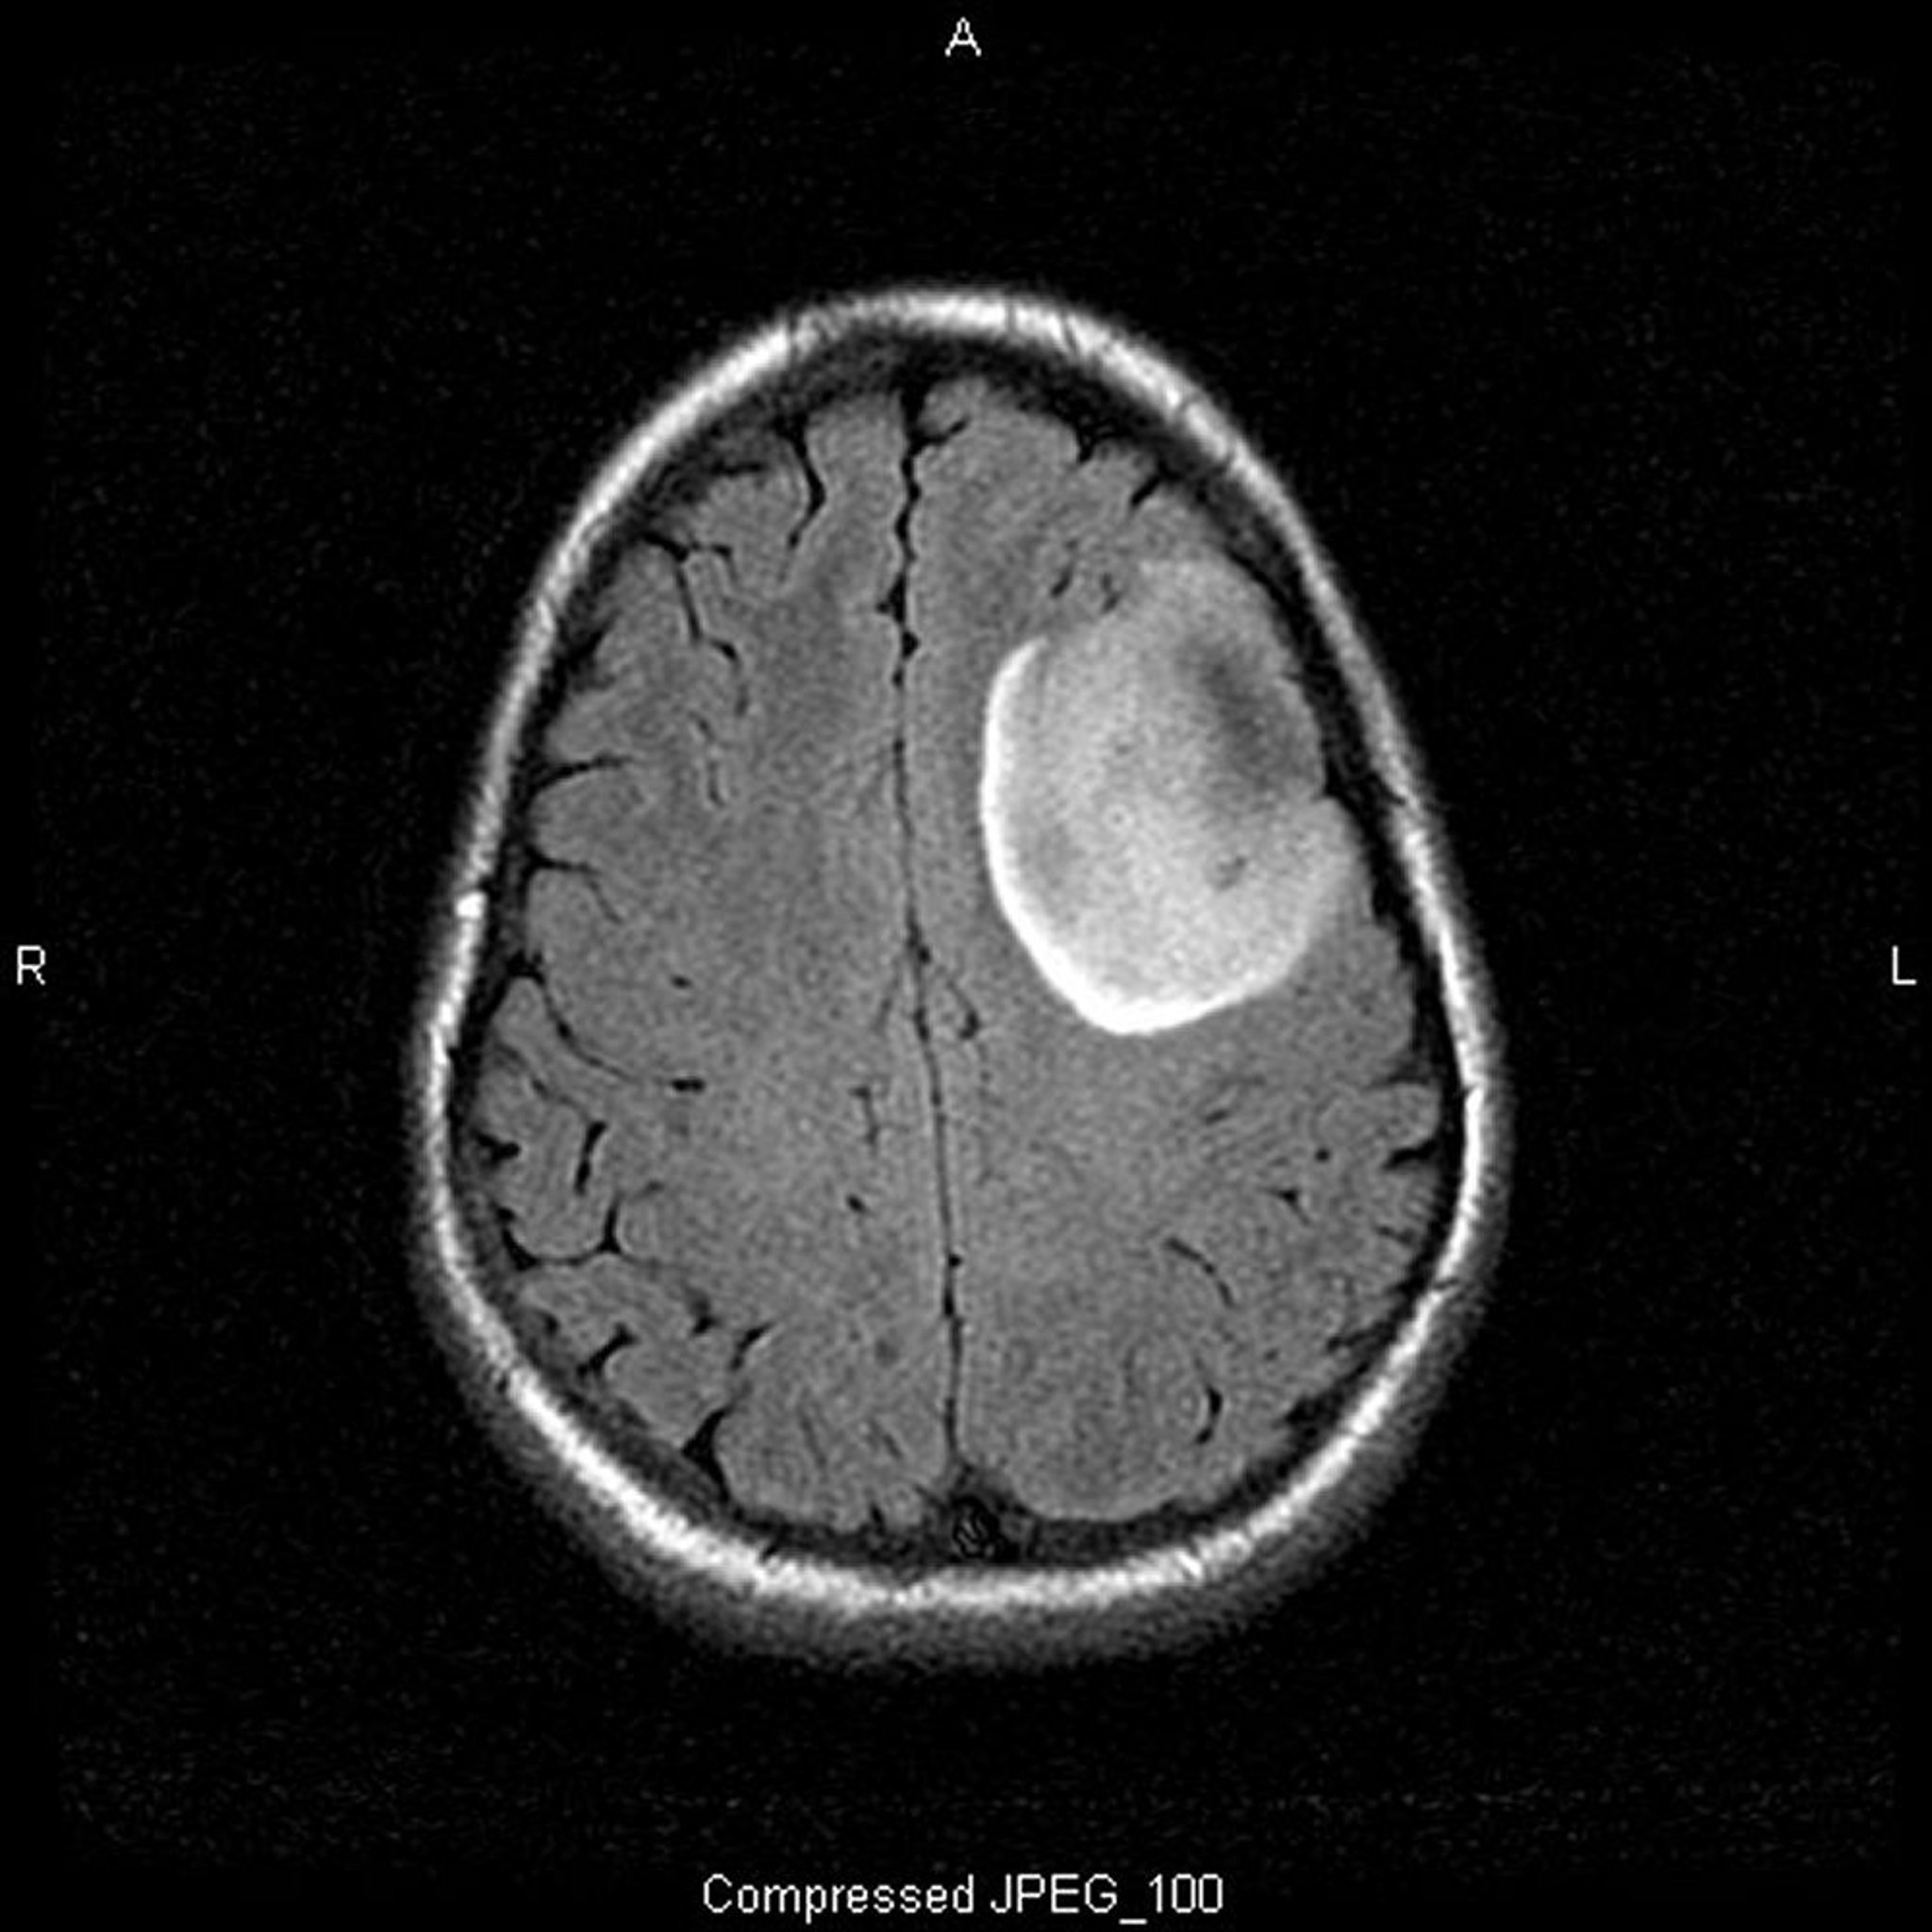

Oligodendroglioma de bajo grado

Esta RM en T2-FLAIR (recuperación de la inversión con atenuación de los líquidos) muestra una señal blanca, que puede indicar una masa o edema. La señal frontal izquierda está muy bien demarcada, lo que sugiere una masa. El contraste no intensifica la imagen. Es un oligodendroglioma de bajo grado (grado II).

Image courtesy of William R. Shapiro, MD.